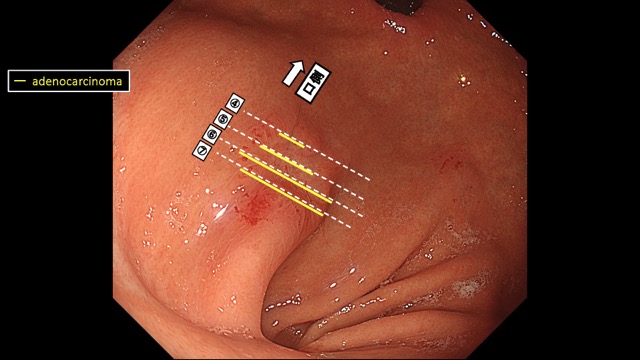

Gastrointestinal Mapping ~Stomach~ 2025.8.27